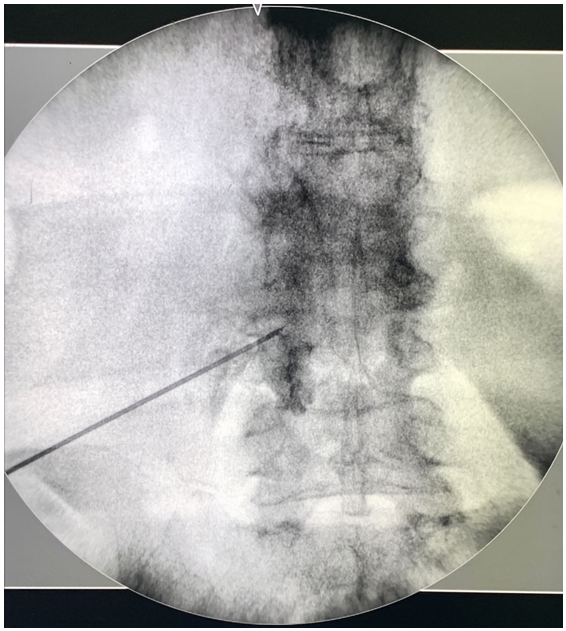

介入治療的常見選擇目前有脊椎硬膜外注射、微創內視鏡手術。硬膜外注射是用麻醉藥物、類固醇針對被壓迫的神經根進行注射。過程中會搭配X光讓醫師能定位神經的位置進行注射。

脊椎硬膜外注射

脊椎硬膜外注射